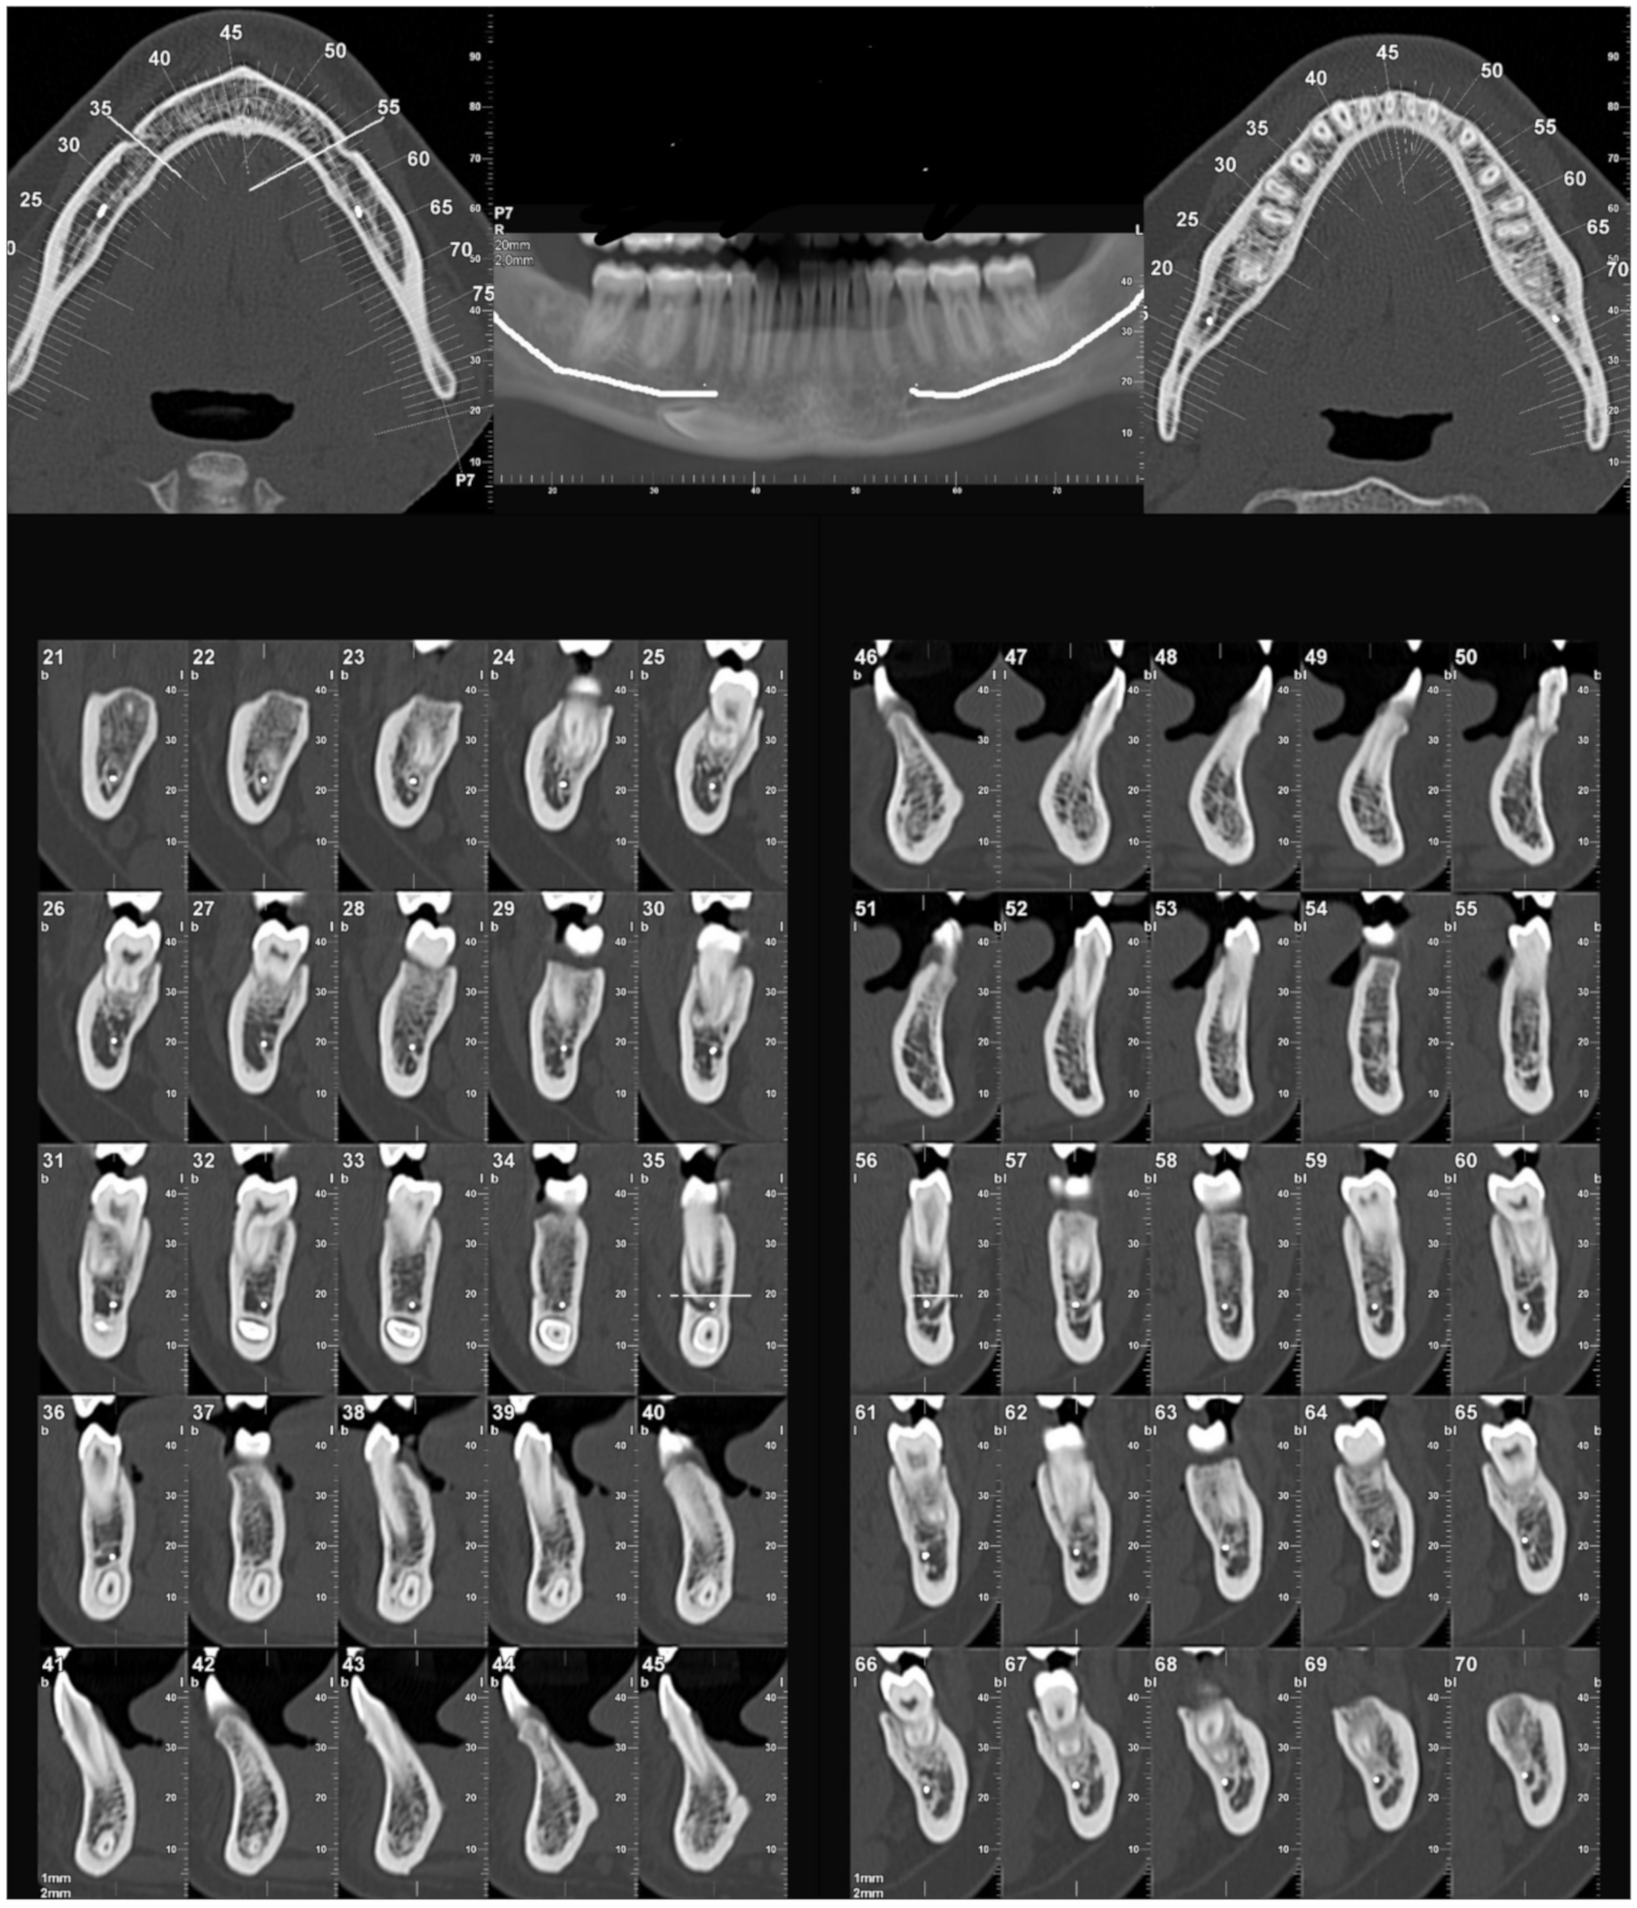

2.3. Evaluation of Radiological Data

- Bertl, M.H.; Frey, C.; Bertl, K.; Giannis, K.; Gahleitner, A.; Strbac, G.D. Impacted and transmigrated mandibular canines: An analysis of 3D radiographic imaging data. Clin. Oral Investig. 2018, 22, 2389–2399. [Google Scholar] [CrossRef] [PubMed]

- Koç, A.; Kaya, S.; Abdulsalam, W.A. Three-Dimensional Analysis of Impacted Maxillary and Mandibular Canines and Evalua-tion of Factors Associated With Transmigration on Cone-Beam Computed Tomography Images. J. Oral Maxillofac. Surg. 2021, 79, 538.e1–538.e11. [Google Scholar] [CrossRef] [PubMed]